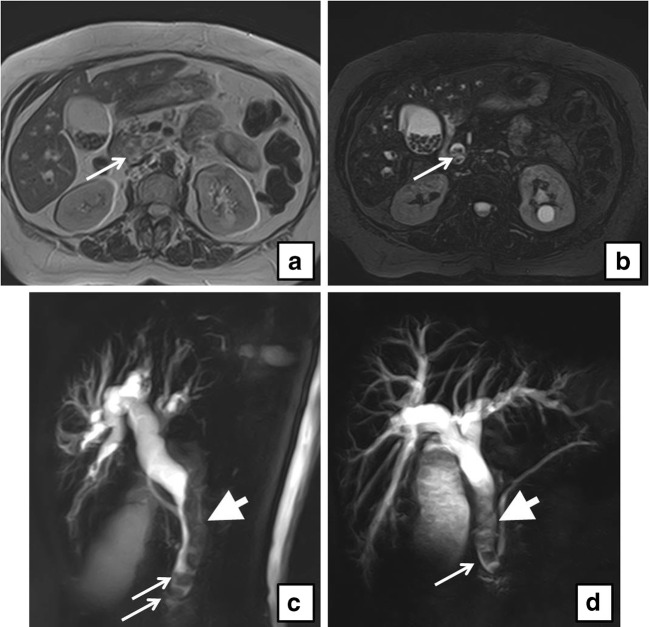

On preoperative US examination, 5 out of 104 patients demonstrated a dilated CBD and, among them, only one patient (20%) presented CBD lithiasis on MRCP, whereas 6 out of 99 patients (6%) with normal choledocal diameter showed CBD lithiasis (Figs. 1, 2, 3, and 4).